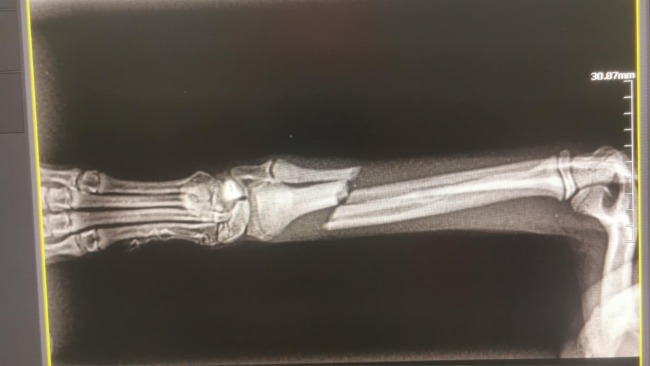

Witam, Mam na imię Tosia, mam niecałe 5 miesięcy, a mój wczorajszy niefortunny skok doprowadził do złamania mojej nóżki w dwóch miejscach ☹️ Jestem malutkim pieskiem ważę zaledwie 1,2 kg. Moja złamana łapka wisi i od wczoraj jestem na lekach przeciwbólowych czekając na operacje. Poniewaz jestem małym pieskiem i mam drobne kostki wiele klinik odmówiło poskładania mojej łapki. Zabieg jest trudny i bardzo kosztowny. W klinice w której jest szansa na ratowanie łapki koszt wynosi 3000-4000 tysięcy za operacje, do tego badania, wizyty kontrolne plus rehabilitacja. Tosia ma miec wstawione dwie płytki Operacja jest na tyle skomplikowana, że nie ma gwarancji powrotu Tosi łapki do sprawności. Robimy wszystko aby uniknąć amputacji. Jest to dla nas ogromny koszt, który będziemy musieli pokryć w najbliższym czasie, bardzo prosimy o pomoc ponieważ są to dla nas kwoty na ten moment nie do osiągnięcia, a chcemy zrobić wszystko aby Tosia mogła cieszyć się życiem ☹️ Na ten moment Tosia ma usztywnioną łapkę i jest na lekach przeciwbólowych.